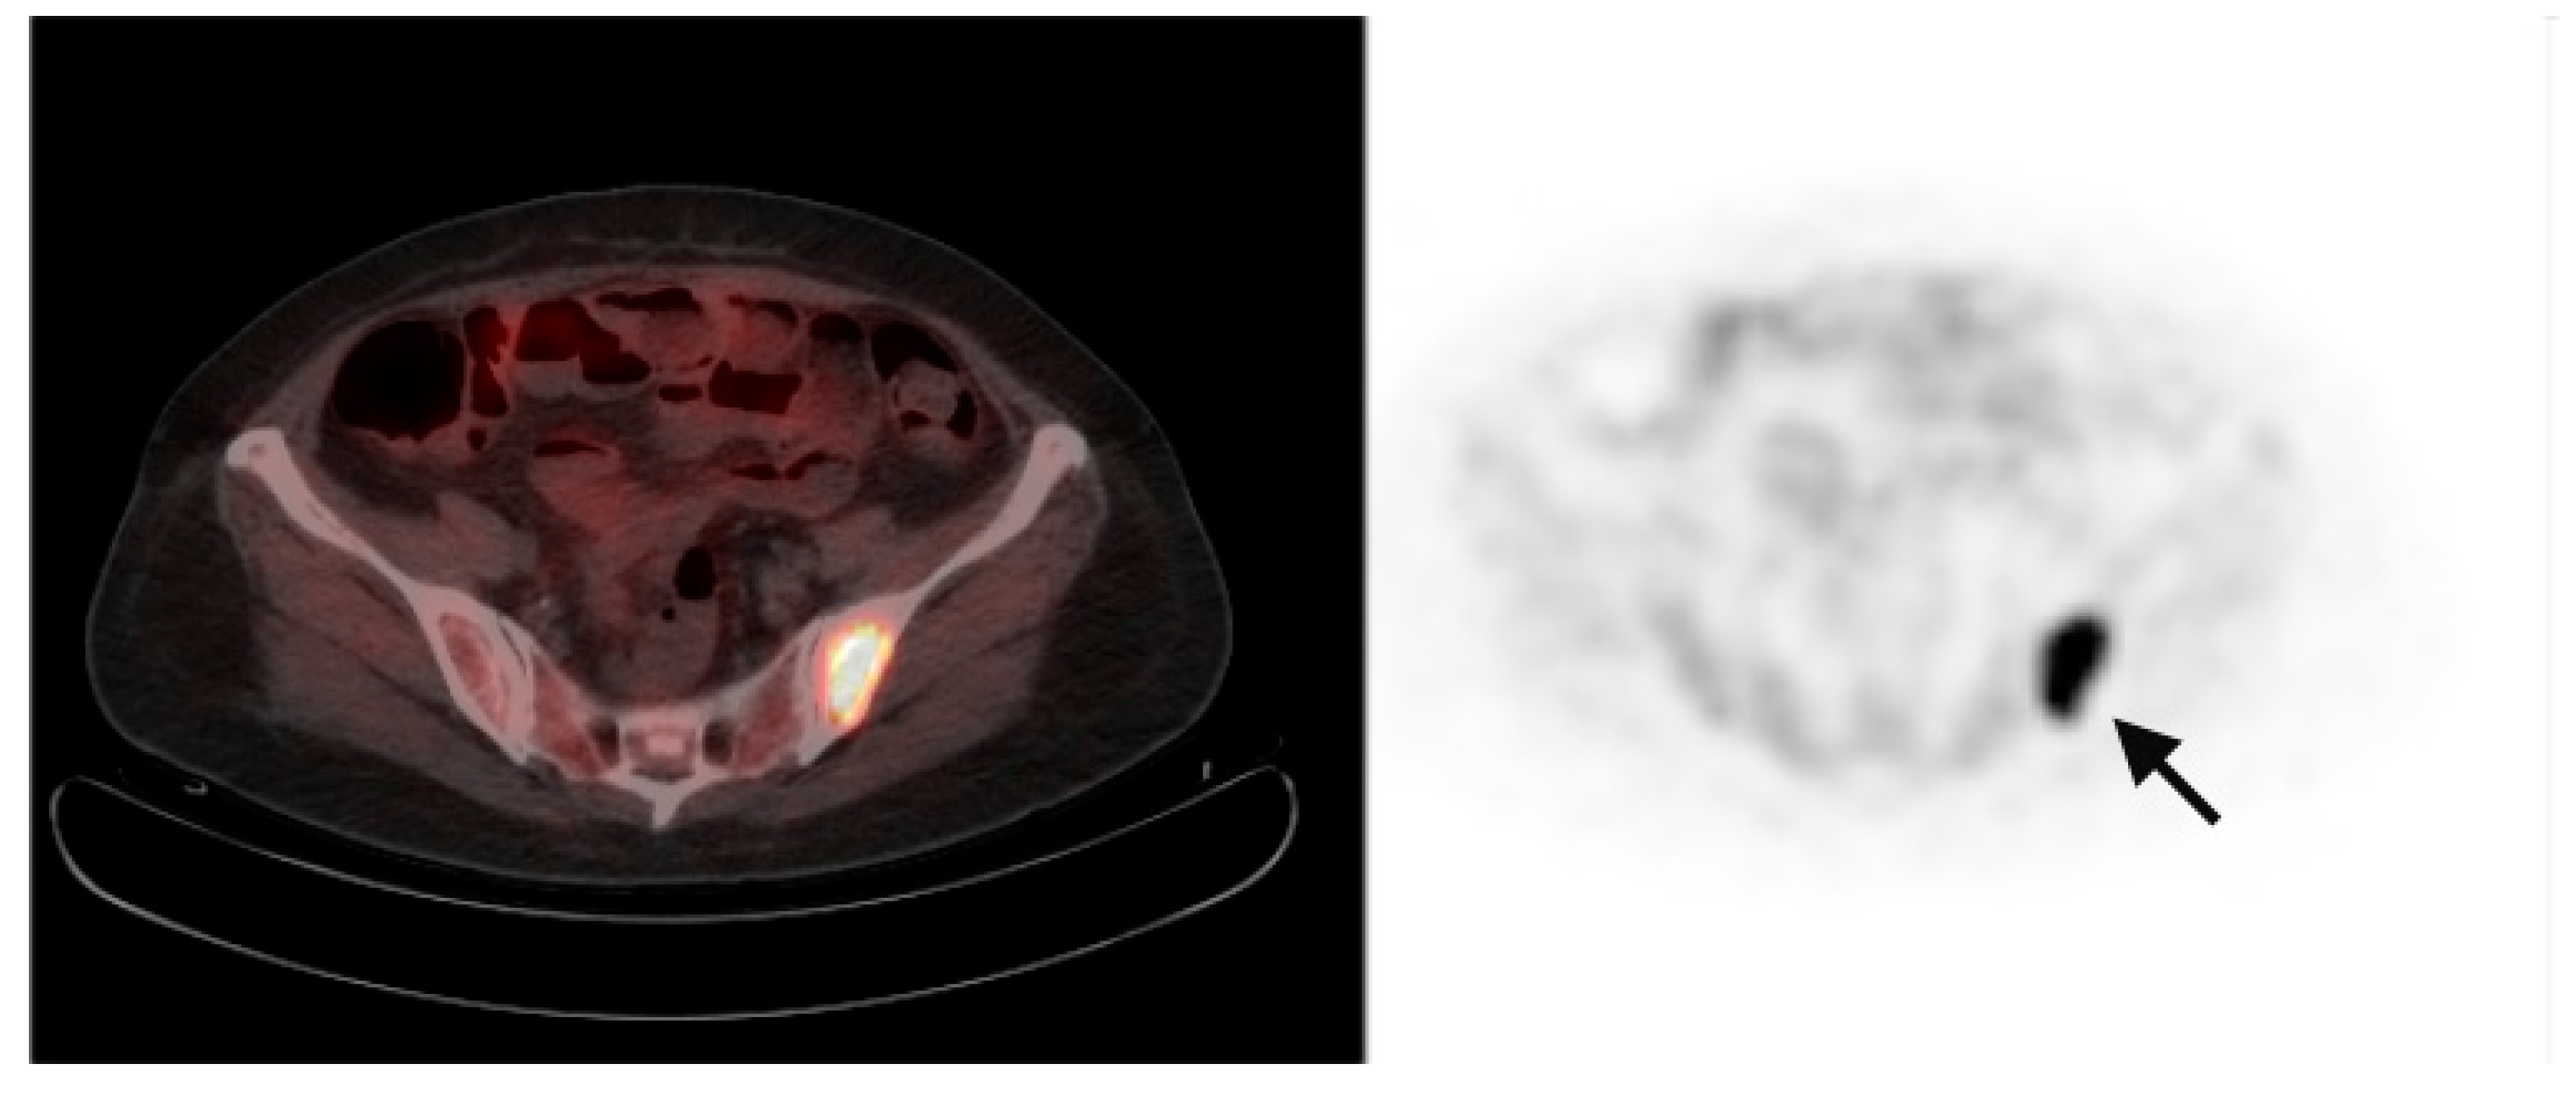

The TBR corresponding to liver tumors ranged from 0.94 to 2.1 (mean 1.6). Corresponding tumor SUVmax ranged from 6.4 to 15.3 (mean 12.1). In 5 (1 newly diagnosed and 4 previously-treated) patients, PET demonstrated increased tissue FCh uptake outside of the liver. Corresponding clinical and radiographic findings in all these patients were consistent with metastatic disease. In 2 previously-treated patients, metastatic disease was seen on FCh PET without any evidence of primary liver tumor recurrence (example, Figure 5). In 6 patients without abnormal FCh uptake on PET, no evidence of recurrent or metastatic disease was noted after 6 months of clinical follow-up.

Figure 5.

Metastatic HCC. Corresponding PET/CT (left) and PET (right) images show abnormal increased FCh uptake in the left posterior ilium (arrow) consistent with the diagnosis of skeletal metastasis.